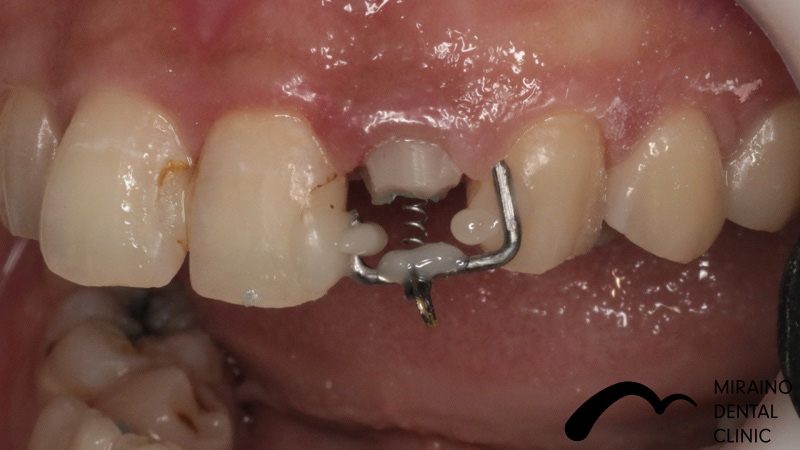

歯の破折予防:MTMの症例

| 施術名 | 歯の破折予防:MTM |

| 施術の概要 | 前歯の差し歯の色が気になるということで来院されました。 噛んだ時に下の前歯が隠れており、治療した歯をより劣化させやすい噛み合わせ[過蓋伵合]の方でした。 歯を失う原因のうち、ムシ歯・歯周病以外に歯への負担荷重お伝えしましたが、 根本的な噛み合わせの治療は希望されなかったため、 次回再発した際は抜歯となる可能性が高いため、なるべく再発しにくい歯科治療を希望され、 MTMを行ったのちメタルフリークラウンでの歯冠修復行いました。 |

クリックして詳細を表示

| 施術の内容 | ムシ歯や歯が折れておりで感染除去後に健康な歯が歯茎の下まで達する場合は、 通常、抜歯もしくは2年以内の抜歯前提の延命治療になってしまいます。 両サイドの歯に表装置をつけ骨からひっぱり出すことで、 歯根破折・歯冠脱離による抜歯の可能性を回避します。 部分矯正MTM(Minor Tooth Movement)の略で、 このような場合エクストルージョン(伾出)と言います。 |

|---|---|

| 1歯あたりの治療費 | 1歯につき50,000円 |

| 考えられるリスク、副作用[歯科治療] | 治療後、痛みや違和感、出血、腫れ、麻痺などが出る事があります。 |

| 考えられるリスク、副作用[全てにおいて] | 必ずしもご希望通りにならない事があります |

| 考えられるリスク、副作用[麻酔] | 麻酔を行う場合、腫れやむくみを生じる事があります。 |

| 考えられるリスク、副作用[噛み合わせ] | また、歯並びが変わる事により違和感を生じる事があります。 |

| 考えられるリスク、副作用[被せ・仮歯] | 仮歯の期間中は仮歯の部分で噛むと破損する場合があります。 |

| 考えられるリスク、副作用[根の治療] | 治療に際して、根の治療が必要になる場合があります。 |